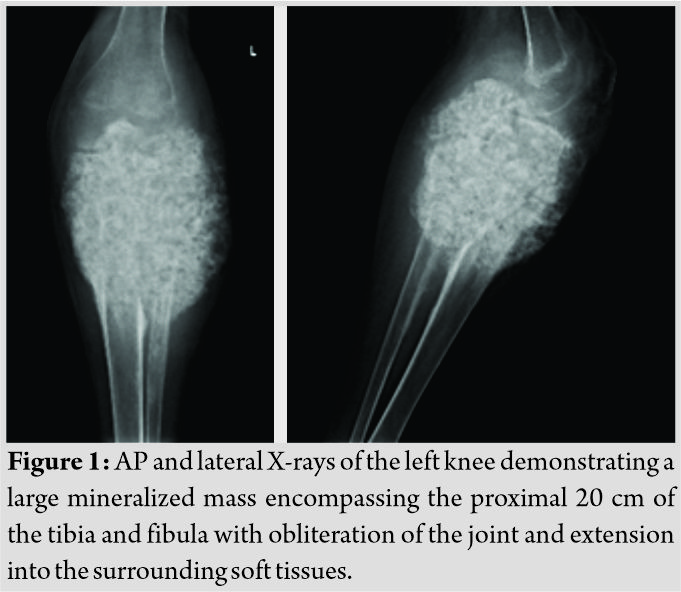

Initial radiographs revealed a large, expansile mass involving the left proximal tibia and fibula with bony destruction and possible intra-articular extension (Fig. 1). It also demonstrated significant soft-tissue extension, mineralization, and periosteal reaction concerning for osteosarcoma. Computed tomography of the chest, abdomen, pelvis, and spine revealed no evidence of metastatic disease. Magnetic resonance imaging revealed a multilobulated, heterogeneous mass measuring 14 cm × 13 cm × 13 cm replacing the left proximal tibia and fibula, with multicompartmental and intra-articular involvement (Fig. 2, 3). It also showed that the distal popliteal neurovascular bundle was posteriorly displaced with full encasement of the anterior tibial artery at the level of the popliteal trifurcation. In addition, the common peroneal nerve was significantly displaced by the tumor and could not reliably be differentiated from the mass. A magnetic resonance angiogram was performed which showed a hypervascular proximal tibial lesion with poor definition of vascular anatomy. A nuclear medicine bone scan was then performed which showed a large expansile mass of the proximal left tibia, fibula, and distal femur with intense radiotracer uptake. The initial radiographic findings were consistent and suggestive of osteosarcoma, and the patient was subsequently scheduled for biopsy.